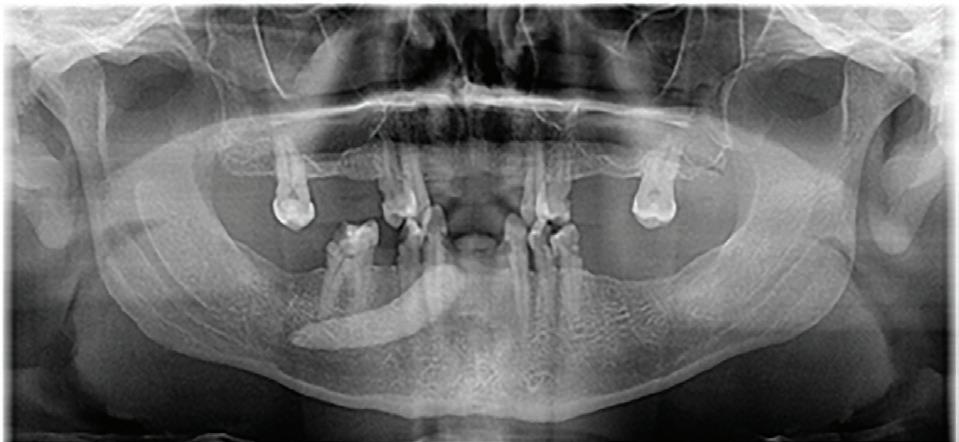

Fig 1. Proximity of root apices to vital structures. A. The periapical radiograph indicates that the apices of the mandibular right second molar and second premolar are in proximity to the inferior alveolar and mental nerves. B. A coronal CBCT image more clearly demonstrates the proximity of the molar apex to the inferior alveolar nerve. C. A coronal CBCT image more clearly demonstrates the proximity of the premolar apex to the mental nerve.

The inferior alveolar canal courses closely beneath the apices of mandibular molars, particularly second molars. Studies have shown that in more than 25% to 30% of patients, the inferior alveolar canal lies within 1 mm of the root apices of second molars; the prevalence is even higher in female and older patients due to reduced bone volume (Fig 1).8

Proper diagnosis is essential to identifying cases at risk of extrusion. Conventional periapical radiography remains a fundamental diagnostic tool in endodontics, offering high-resolution, real-time imaging at low radiation exposure and minimal cost. However, the 2-dimensional (2D) nature of periapical radiographs presents inherent limitations when complex root anatomy is evaluated, especially in the apical third.

One of the most significant shortcomings of periapical radiography is its inability to provide information in the buccolingual dimension. This makes it difficult to detect resorptive lesions (internal or external) located on the buccal or lingual surfaces; fenestrations or dehiscences in the cortical plate; split canals, C-shaped canals, or isthmuses hidden in a single projection; and superimposed anatomical structures, including the zygomatic arch over maxillary molars or mental foramen overlapping premolar apices.

To improve diagnostic accuracy, clinicians are encouraged to take multiple angulated views. However, even with angulated views, the 2D limitation persists, and structures with significant buccolingual spread or overlap may still be misinterpreted. In cases in which a patient’s symptoms persist despite normal

radiographic findings, or an apical resorption, a fenestration, or an anatomical anomaly is suspected, reliance on periapical radiographs alone may result in missed diagnoses or mismanagement (Fig 4).

Additionally, periapical radiographs may underestimate the extent of periapical bone loss or resorption if confined to the cortical plate or masked by trabecular density. For instance, studies have shown that periapical radiolucencies must involve at least 30% mineral loss in the bone to be radiographically visible.24,25